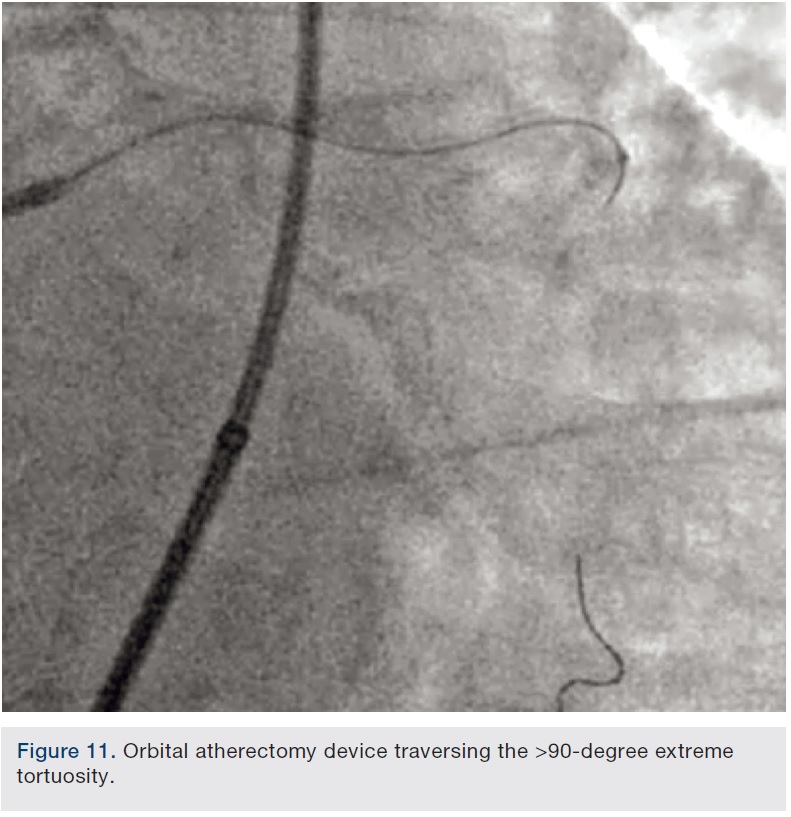

Preparation of this vessel was completed with atherectomy in order to facilitate stent delivery and optimal stent expansion. The Diamondback 360 orbital atherectomy system (CSI) was chosen, given the severe tortuosity. With the orbital device, there is a leading edge bushing ahead of the “working area” of the device, which prevents the wire from being cut on tortuous turns. A 1.25 mm device was used and was delivered around the most extreme portion of the tortuous vessel where the critical lesion was located. Several runs on low and high were performed (Figures 10-11). We then dilated the lesion with a 3.0 mm balloon, and angiography showed adequate balloon expansion (Figure 13). A GuideLiner (Vascular Solutions) was placed prior to stent delivery to increase chances of stent delivery, but also to decrease the chance of stent embolization if the stent had to be withdrawn. A 4.0 x 28 mm Promus Premiere stent (Boston Scientific) was then delivered fairly easily with good stent expansion (Figure 14) and the procedure was finished safely (Figure 15).